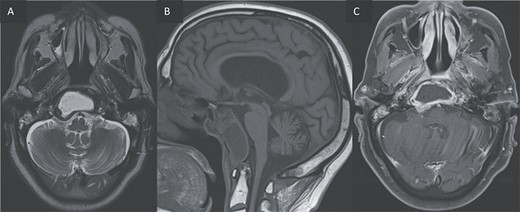

Furthermore, inflammatory changes were noted to extend into the petrous, tympanic, and mastoid segments of the right temporal bone, as well as involving the petrous and mastoid regions of the left temporal bone and the occipital bone. Additionally, small abscess cavities were observed within the right occipital condyle.

T2 coronal (A) and T1 post gadolinium axial images (B, C) showing the extension of the inflammation around the clivus and in the petrous, tympanic, and mastoid portions of the right temporal bone with small abscesses along the mastoid cells and the occipital bone.